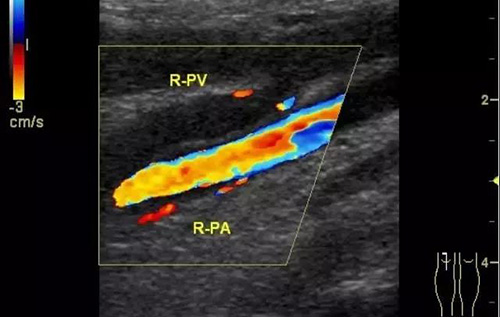

彩色普勒超聲診斷儀,線陣探頭,頻率7.5~10MHz。受檢查者先取仰臥位,患肢髖關(guān)節(jié)略外旋,大腿輕度外展且膝關(guān)節(jié)略曲,使整個(gè)下肢呈松弛狀態(tài)。自上而下順序檢查髂外、股總、股淺、股深及大隱靜脈;之后取俯臥位,檢查靜脈及小腿靜脈。以縱切和橫切顯示血管,灰階超聲主要觀察血管內(nèi)徑、管壁結(jié)構(gòu)及血栓情況,CDFI主要觀察管腔內(nèi)有無血流顯示、充盈缺損及血液返流情況,必要時(shí)擠壓小腿腓腸肌以利血流顯示。

彩色多普勒超聲具有很高的特異性和敏感性,是超聲診斷技術(shù)的重要發(fā)展。

彩超診斷下肢深靜脈血栓形成后綜合征具有無創(chuàng)、實(shí)時(shí)、動(dòng)態(tài)、重復(fù)性好、準(zhǔn)確率高的特點(diǎn),且能充分了解血管內(nèi)外的解剖學(xué)改變,觀察靜脈管壁、血流充盈、靜脈瓣返流程度以及側(cè)支循環(huán)是否建立和血栓的溶液情況,可直觀地觀察到血流動(dòng)力學(xué)改變,所以具有很高的使用價(jià)值。通過對(duì)治療前后聲像圖的對(duì)比,可以提示臨床的治療效果,對(duì)于臨床治療具有很大的指導(dǎo)作用。